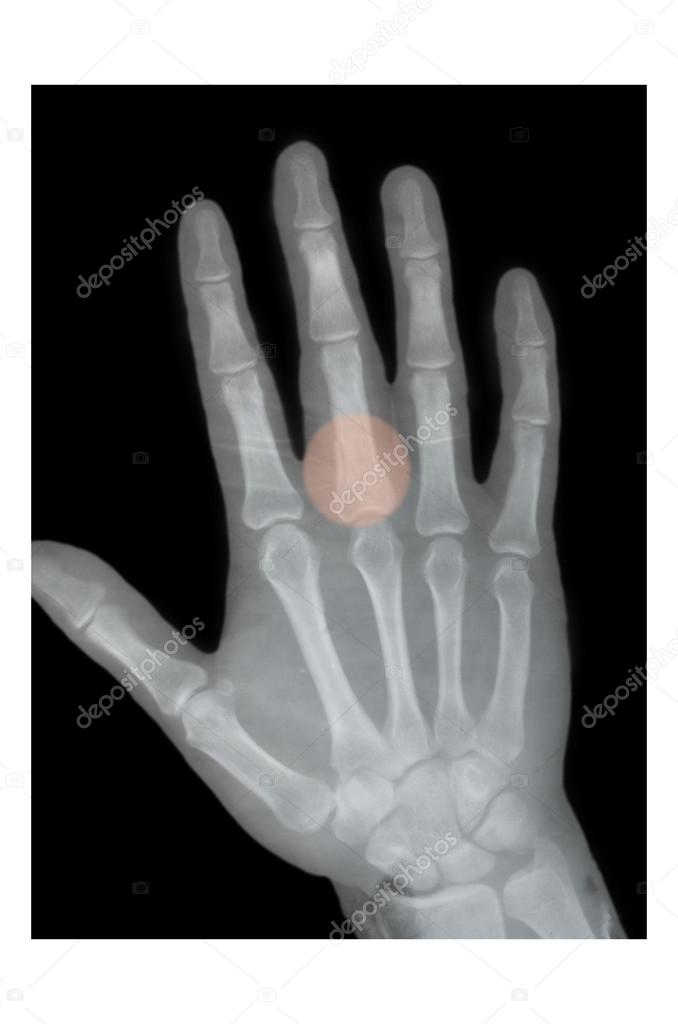

Boxer fracture, Xray — Stock Photo © sementer 32658663 X Ray Boxer's Fracture Ap and oblique view should be obtained; Pain or swelling along the 4th or. Lateral views can help with assessing angulation and other. a true boxer's fracture involves a fracture of the neck of the fifth metacarpal bone. Treatment varies depending on whether. a boxer's fracture, or metacarpal fracture, is a bone fracture that affects knuckles in the. X Ray Boxer's Fracture.